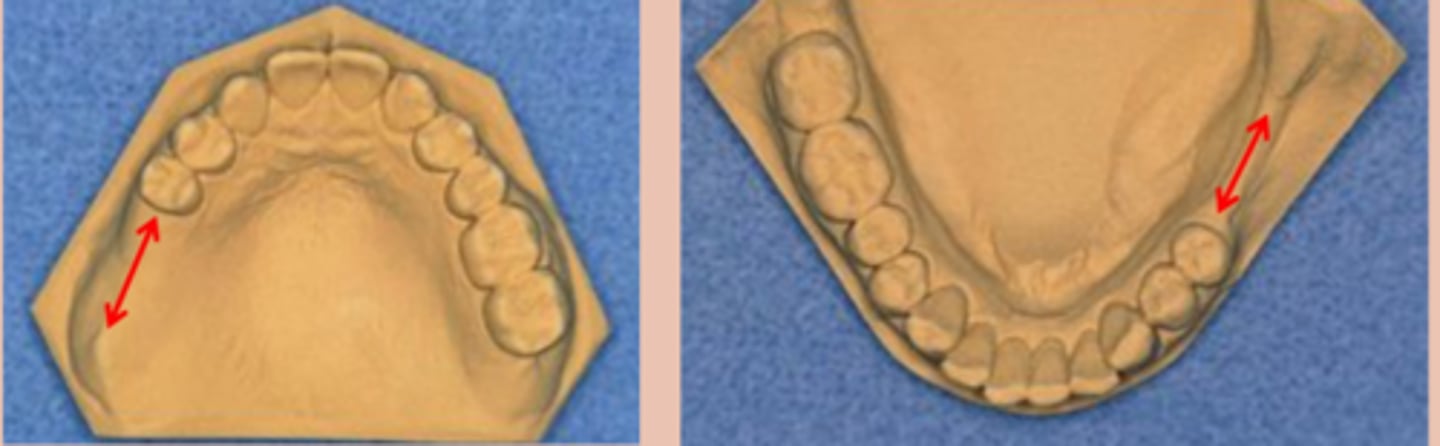

Kennedy Class I

Tooth and tissue supported:

bilateral edentulous area posterior to natural teeth

unilateral edentulous area located posterior to the natural teeth

Kennedy Class III